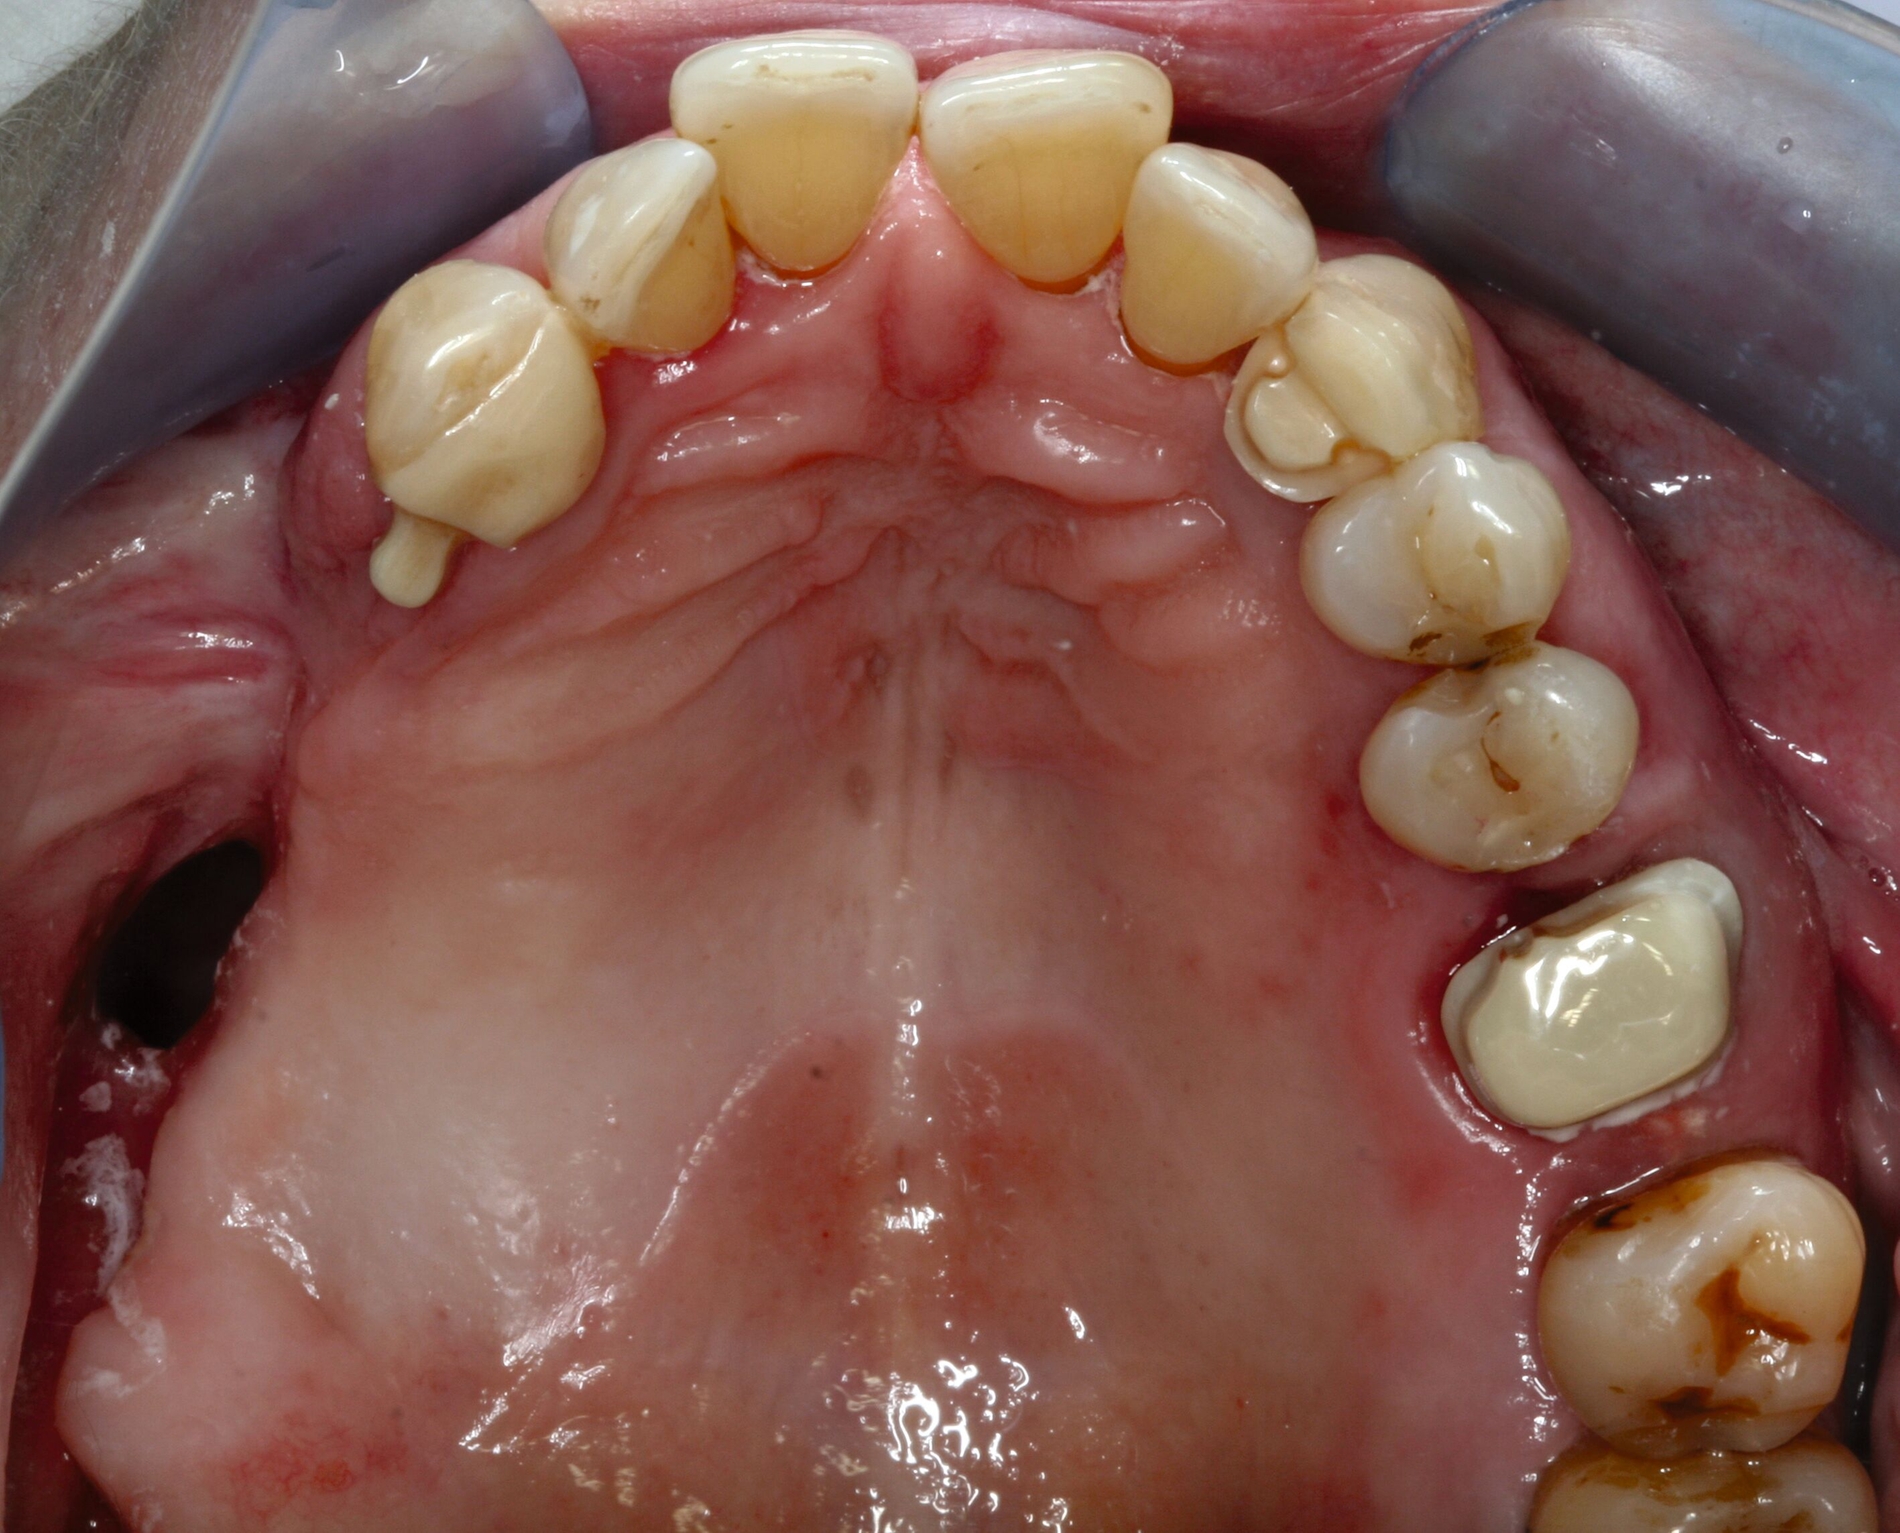

Nach siebenjähriger Tragezeit reduzierte sich der Allgemeinzustand der Patienten bedingt durch einen zweifachen Apoplex erheblich. Die Angehörigen bemühten sich bei nun fehlender Eigenverantwortlichkeit der Patientin um eine dauerhafte Aufnahme in eine Pflegeeinrichtung. Eine Vorstellung zur zahnärztlichen Kontrolle erfolgte nicht und die Patientin konnte unter ihrer ursprünglichen Adresse nicht mehr erreicht werden. Nach eineinhalbjähriger Abwesenheit wurde die Patientin mit Unterstützung ihrer Angehörigen wegen reduzierter Nahrungsaufnahme aufgrund von Schmerzen zur zahnärztlichen Behandlung vorstellig (Abbildung 3). Bei stark reduzierter Therapie- und Mundhygienefähigkeit wurde zusammen mit den Angehörigen entschieden, mehrere stark kariös und parodontal geschädigte Zähne zu entfernen und den vorhandenen Zahnersatz umzuarbeiten. Es lag nun eine BS 3 bis 4 vor.